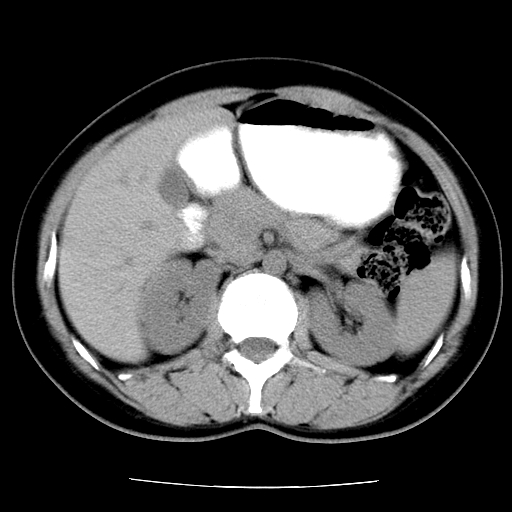

标题: CT16892:女40Y,急性阑尾住院!

女40y,急性阑尾住院!术前发现请会诊!

考虑门静脉瘤样扩张可能,建议增强扫描

胰头假性囊肿也有可能,建议增强

病灶位于门静脉的位置 ,有层面显示血管夹层样改变 ,考虑是门静脉瘤样病变1

病灶位于门静脉的位置 ,有层面显示血管夹层样改变 ,考虑是门静脉瘤样病变,建议进一步增强ct检查。

肝门区囊性占位,壁有钙化,考虑良性。来源难定。